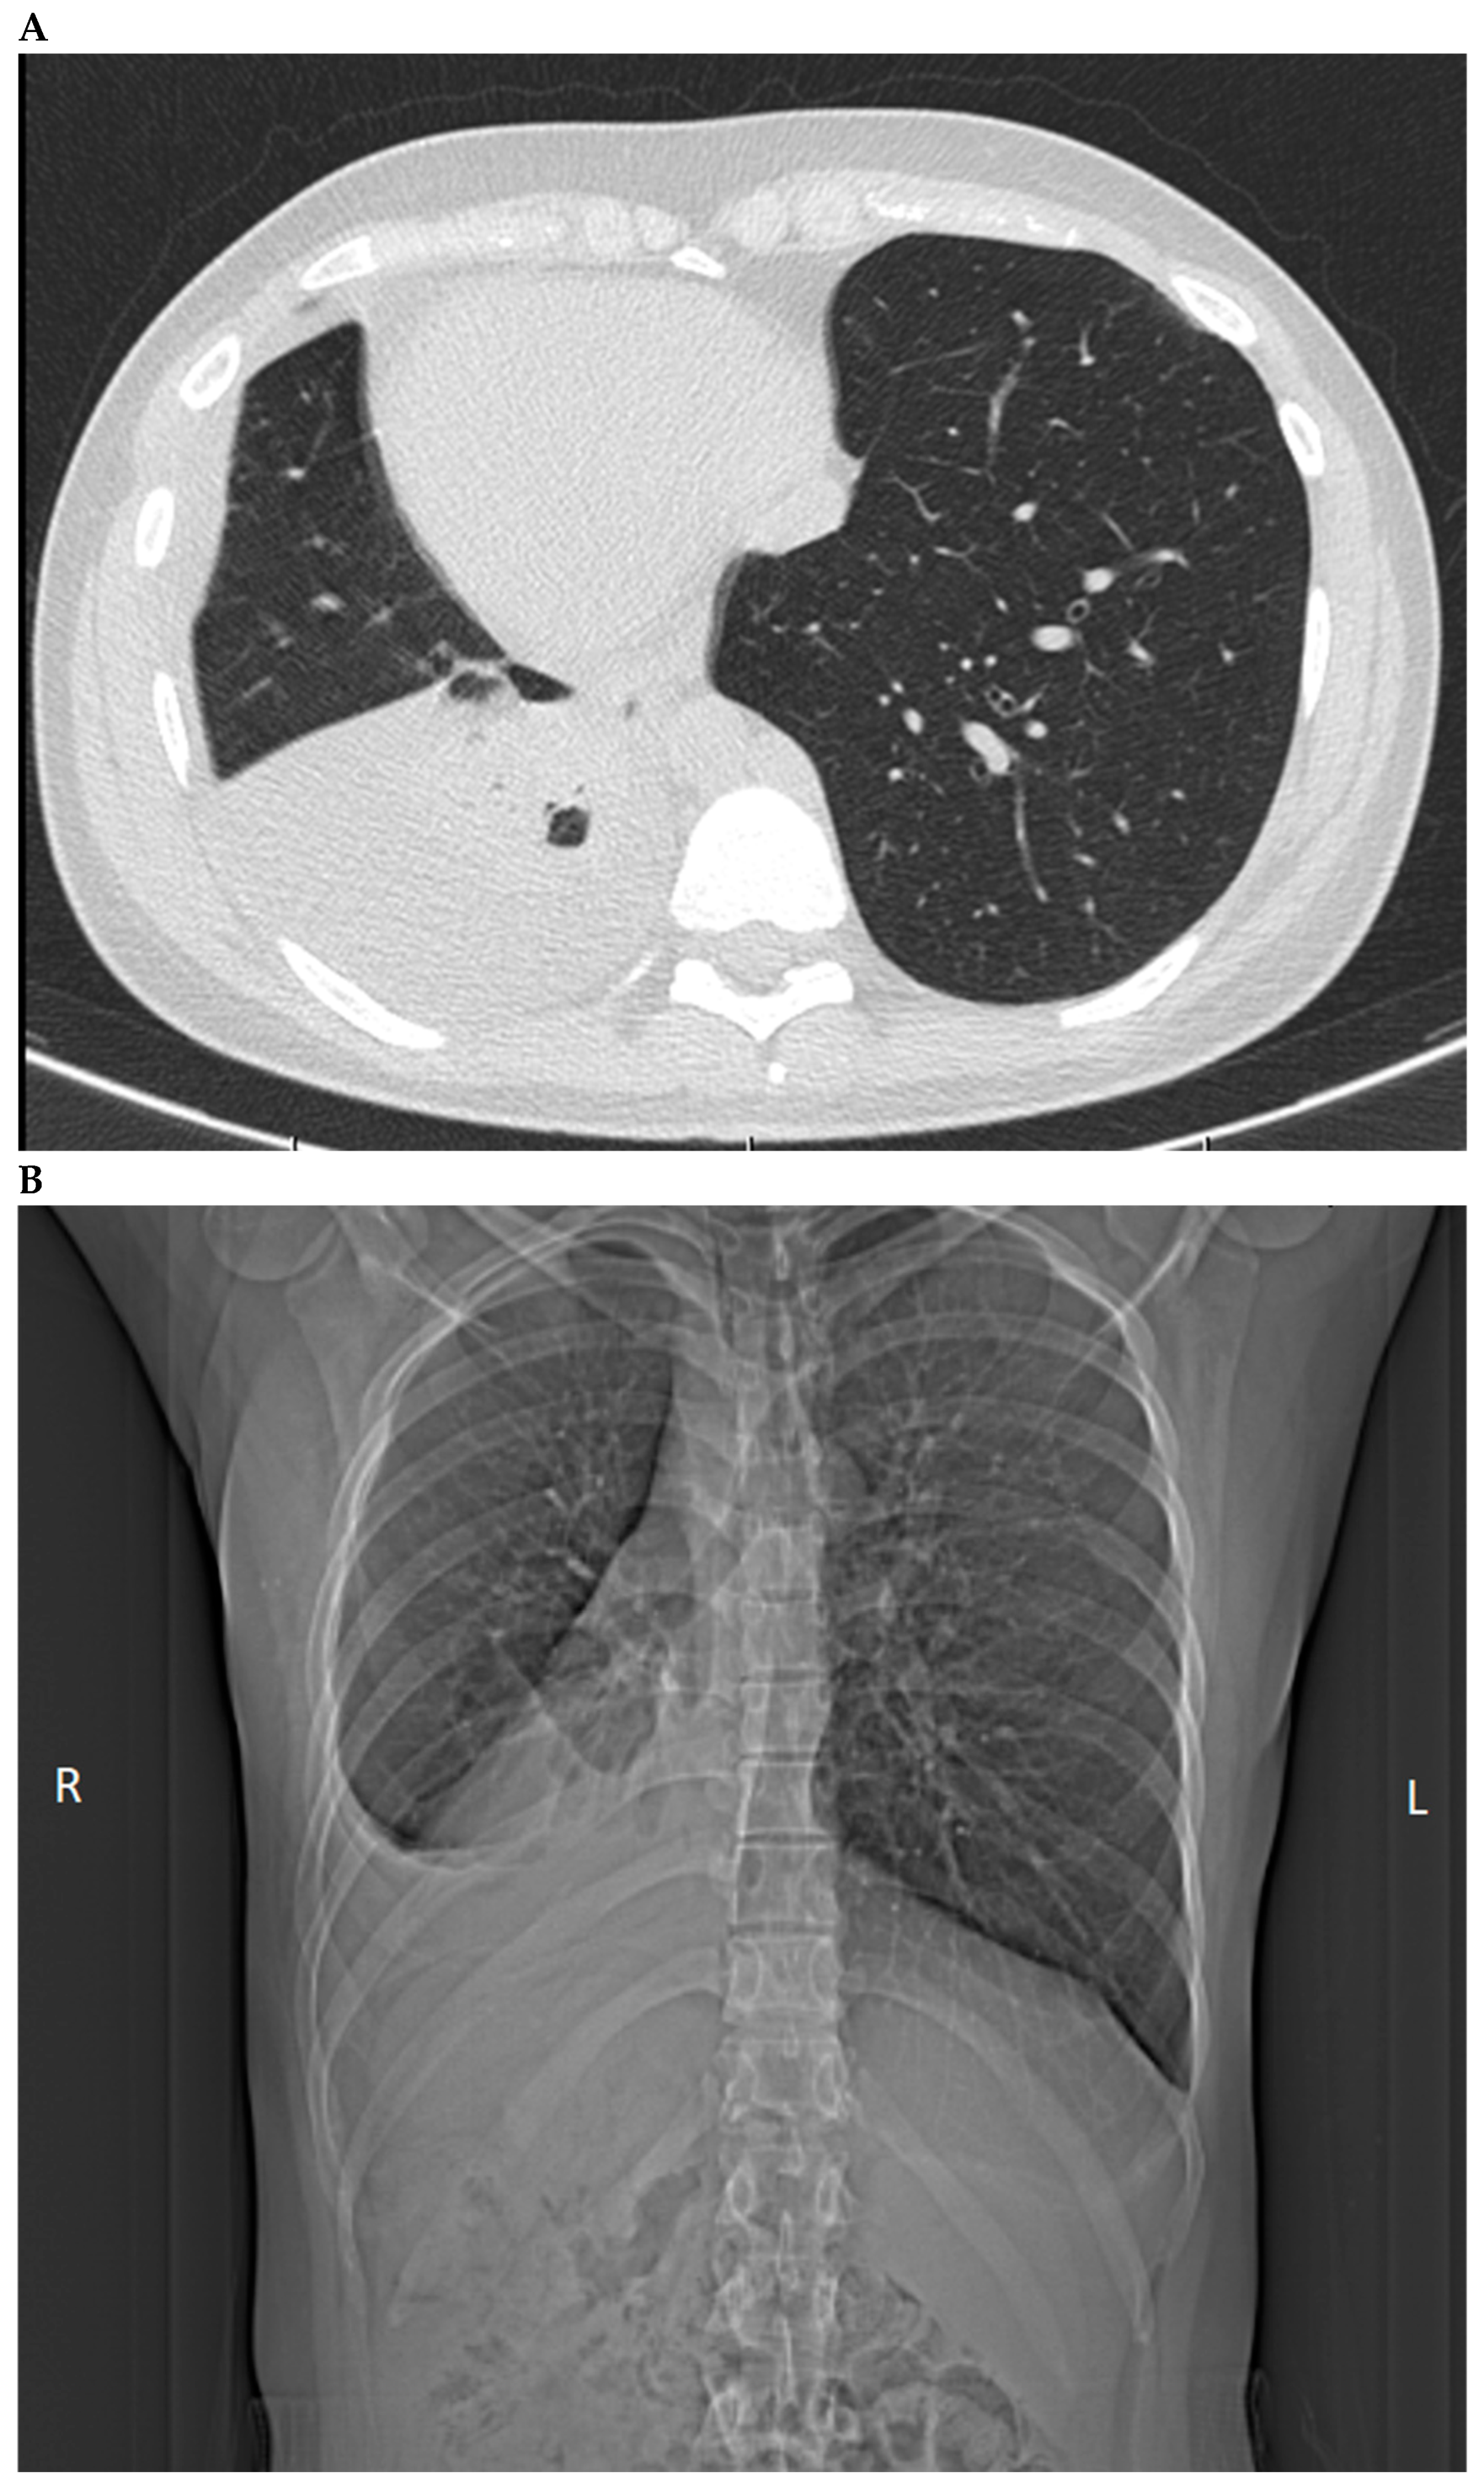

| Chest CT (without contrast enhancement) | - | 23 April 2024: Exudative pleurisy of the right pleural cavity, associated with Löffler’s syndrome (eosinophilic pneumonia in the context of toxocariasis). Situs inversus with pulmonary inversion. The heart and aortic arch are on the right side. The liver is on the left side, and the spleen is on the right. Fluid is present in the right pleural cavity, up to 40 mm in thickness. It was noted that there are atelectatic/inflammatory changes in the lower lobe of the right lung with an accompanying layer of fluid in the right pleural cavity. No enlarged lymph nodes in the mediastinum. The heart is not enlarged, there is no fluid in the pericardial sac, and the aorta is not dilated. The right kidney shows a segmentally thinned cortical layer with hypodense areas, most likely cysts. Bone structures show no pathological changes.  | - |

| Chest X-ray | 5 April 2024:  Fluid in the right pleural cavity, extending up to the ninth rib and entering the oblique fissure. Pulmonary field without focal lesions. Cardiac silhouette within normal limits.  | 22 April 2024:  In the right pleural cavity, fluid up to 29 mm in width is present. No fluid observed in the left pleural cavity. 26 April 2024: In the right pleural cavity, fluid up to 45 mm in width is present. No fluid is observed in the left pleural cavity.  | 24 June 2024:  No signs of fluid were observed in the right or left pleural cavity.  |